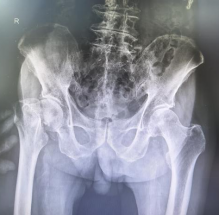

术前X线示:右股骨颈骨折

术后X线